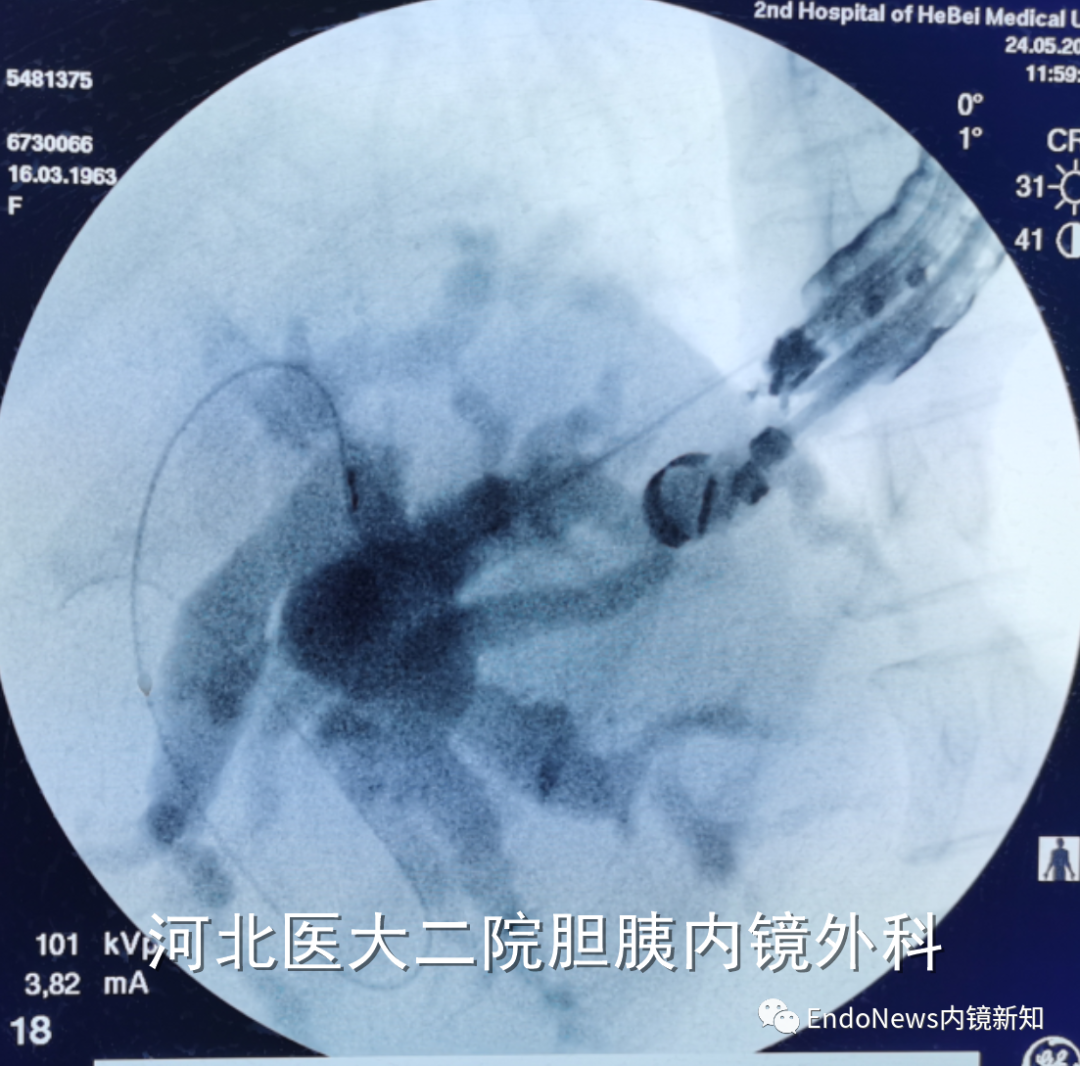

幸运的是,此患者第一针穿刺即成功,随后注射造影剂(EACP),显影后可观察到如图1(a)中所示,这个患者肝内胆管分支很多,但是由于每支均比较细,不容易找到理想的目标穿刺胆管。

下一步进入导丝之后,我们发现导丝朝向胆管上游(即肝缘方向,如图1(b)中所示),这时需要用到此前提到的调整方法:将穿刺针和导丝往回撤,尤其穿刺针,要撤入到肝实质内,但要注意导丝不能往回撤太多,这个过程一定要在X线下谨慎操作。

如图1(c)中所示,导丝如果完全撤出胆管,极有可能脱出,因此我们应及时再次进导丝,如图1(d)中所示。

但是进导丝之后,我们发现导丝再次朝向远端胆管,但仔细观察,发现导丝的弯曲部分的方向是朝向胆管下游的,恰好符合我们的目标方向,这时只需要继续进导丝即可。这个时候其实导丝是打着弯朝胆管下游方向前进的(如图1(e)中所示),这是安全的情况,就如同ERCP时我们进胰管一样,如果其弯头的方向是往胰管上游走的,无需担心脱出或者穿出到其他地方。